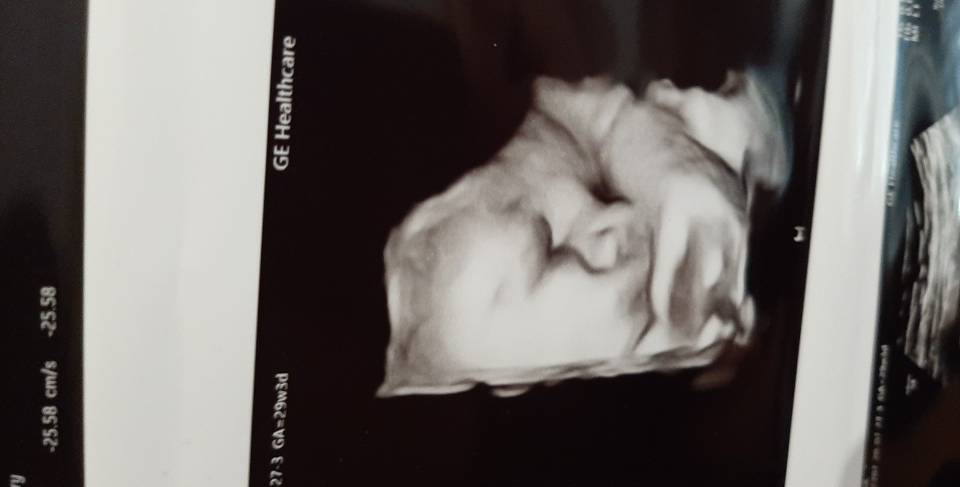

Hej. Też miałam wam napisać. Byliśmy na wizycie w 29+3. Jest chłopak z widocznymi jajkami [emoji23] W w9+3 ważył 1710g i zapowiada się że małym kabanem [emoji23][emoji23] Trochę zaspany na zdjęciu [emoji16]